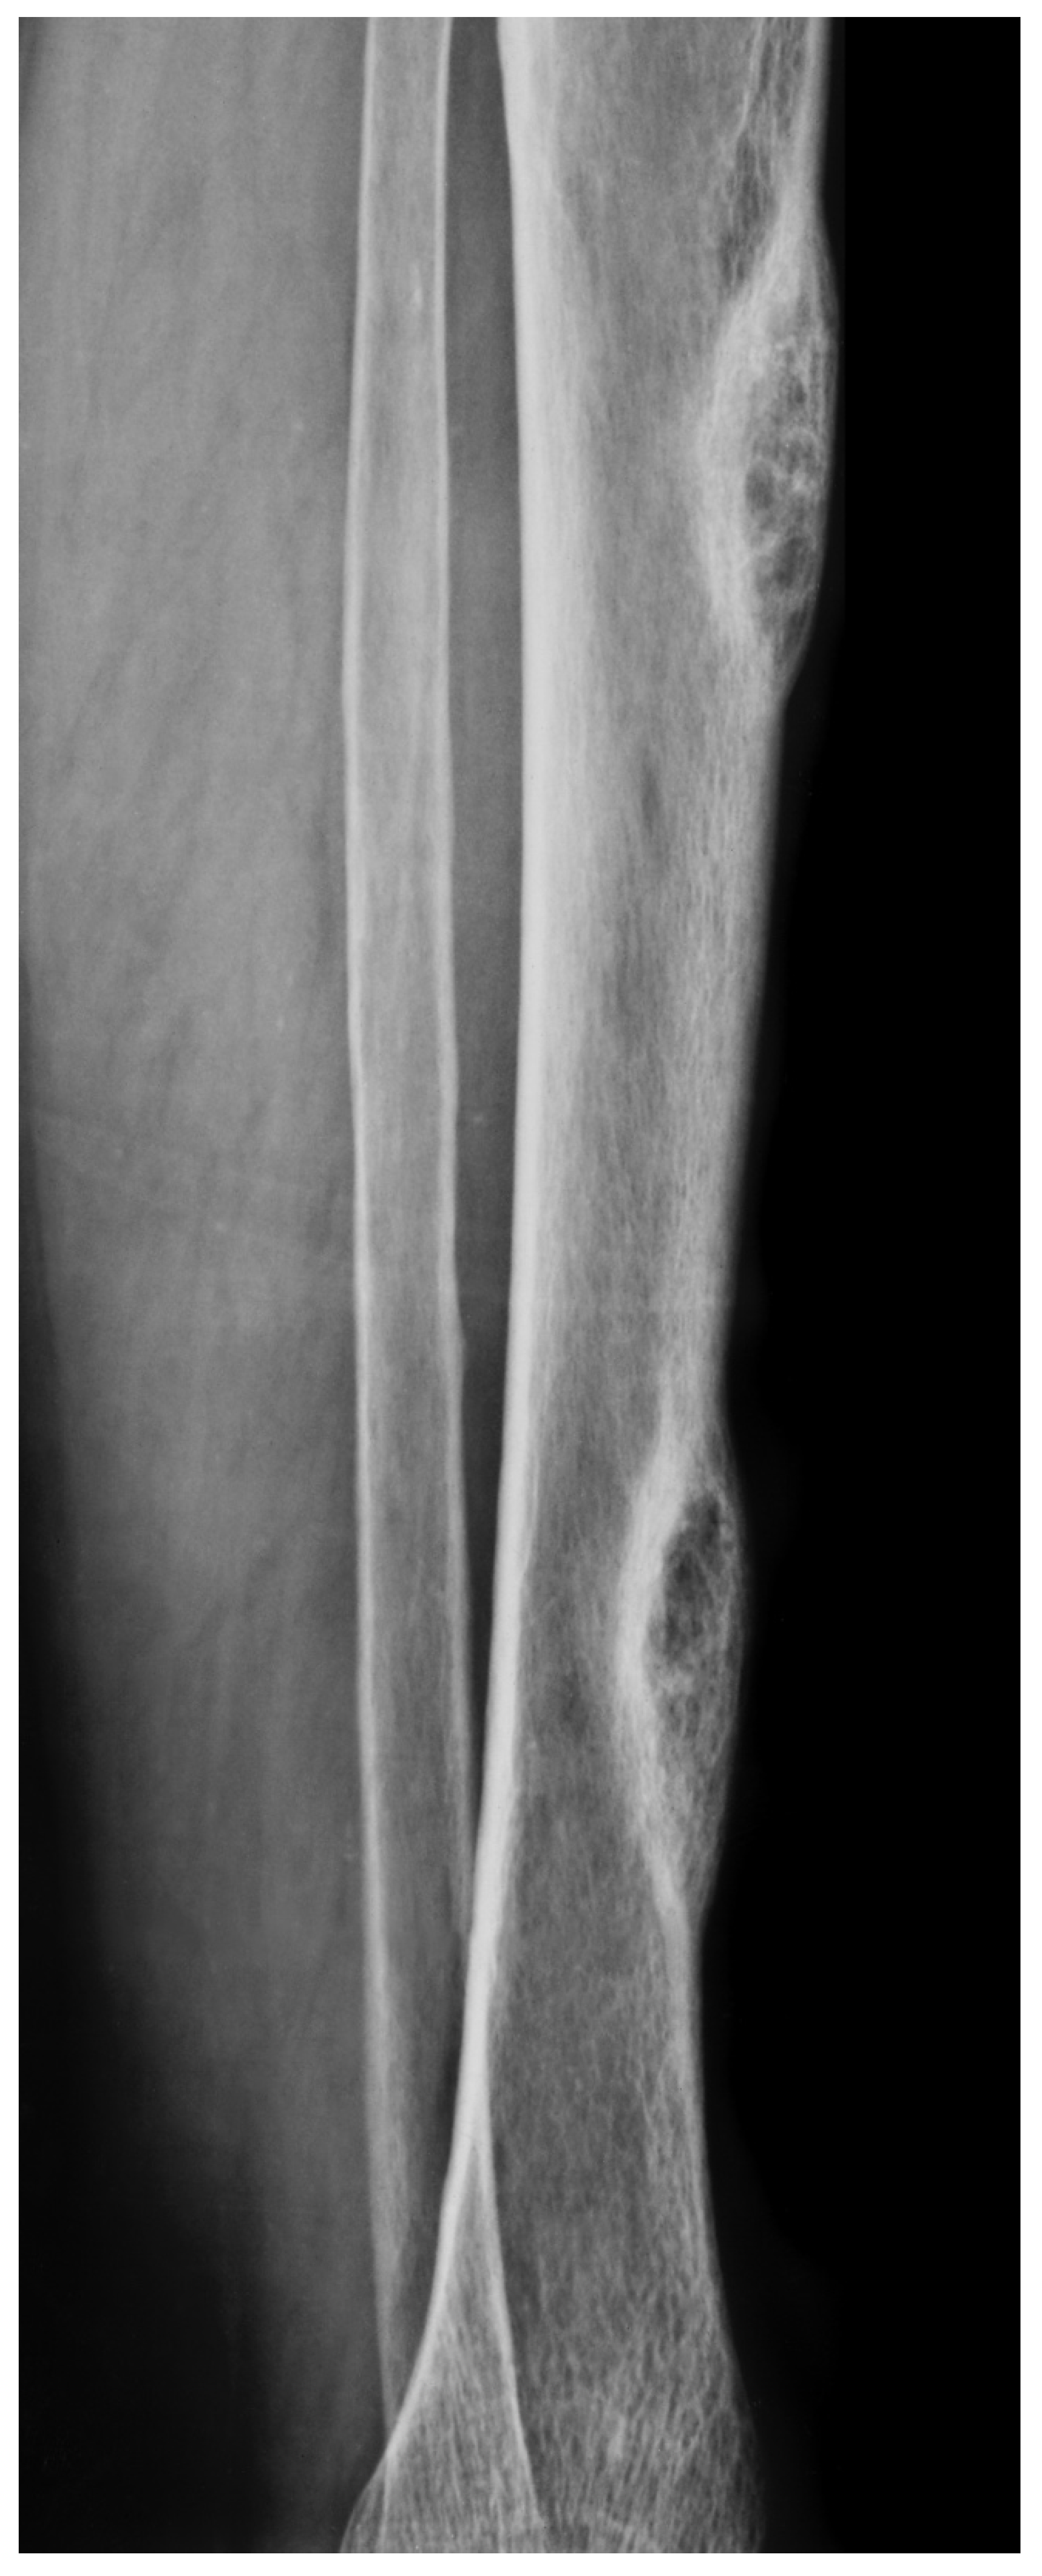

Figure 3. A. X-ray of a 70-year-old female showing two diaphyseal cortical radiolucency’s with a thick radiopaque inner margin. B. Histology of a typical brown tumour associated with hyperparathyroidism showing scattered multinucleated osteoclasts in a slightly storiform arranged background of spindled and rounded pre-osteoclasts.